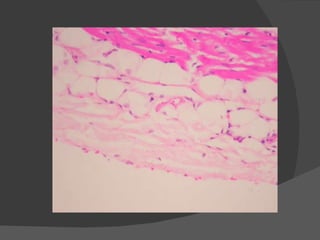

HISTOLOGIA DEL CORAZÓN El corazón es un órgano compuesto de adentro hacia afuera por las siguientes capas histológicas: Endocardio : epitelio simple plano y fibras colágenas. Miocardio : muscular. Epicardio : composición similar a la del endocardio.

Endocardio Se continua con la túnica intima de los vasos sanguíneos que llegan y salen del corazón. Se compone de un endotelio, que es un epitelio escamoso simple y una capa subyacente de tejido conectivo fibroelastico con fibroblastos dispersos.

Más abajo yace una capa de tejido conectivo denso que contiene abundantes fibras elásticas entremezcladas con células de musculo liso. En lo profundo, al endocardio se encuentra una capa subendocardica de tejido conectivo laxo que contiene vasos sanguíneos pequeños, nervios y fibras de Purkinje del sistema de conducción del corazón.

EPICARDIO La capa mas externa de la pared del corazón, también se denomina capa visceral del pericardio (compuesta por un epitelio escamosos simple conocido como mesotelio).

La capa subepicárdica de tejido conectivo laxo contiene vasos coronarios, nervios y ganglios. En las raíces de los vasos que penetran y salen del corazón del corazón el  pericardio visceral  se continúa con la capa serosa del  pericardio parietal ( en raíces de vasos). Estas dos capas del pericardio  encierran la cavidad pericárdica (espacio con cantidad pequeña de líquido seroso para lubricar la capa serosa del pericardio y pericardio visceral).